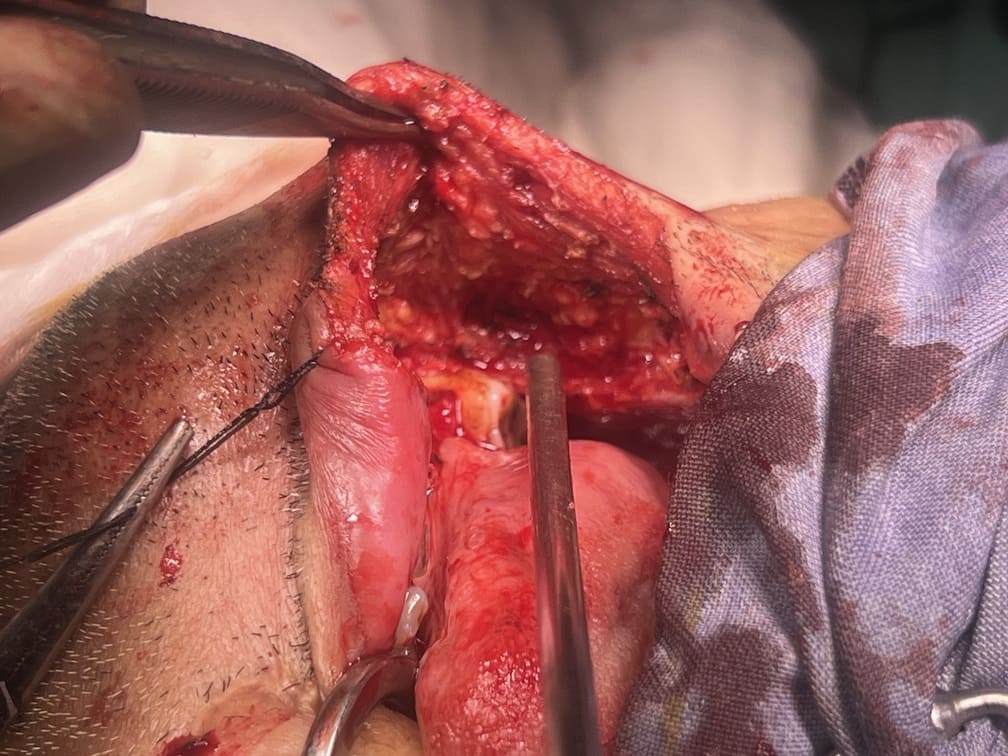

57 years old female suffering from left buccal mucosa growth involving left RNT and gingival surface of lip extending up to right angle mouth.left modified neck dissection with left distal segmental mandibulectomy with wide excision of left buccal mucosa with left RMT growth with excision gingival margin of lower lip with left pectoralis with right nasolabial flape done.

29-12-2025